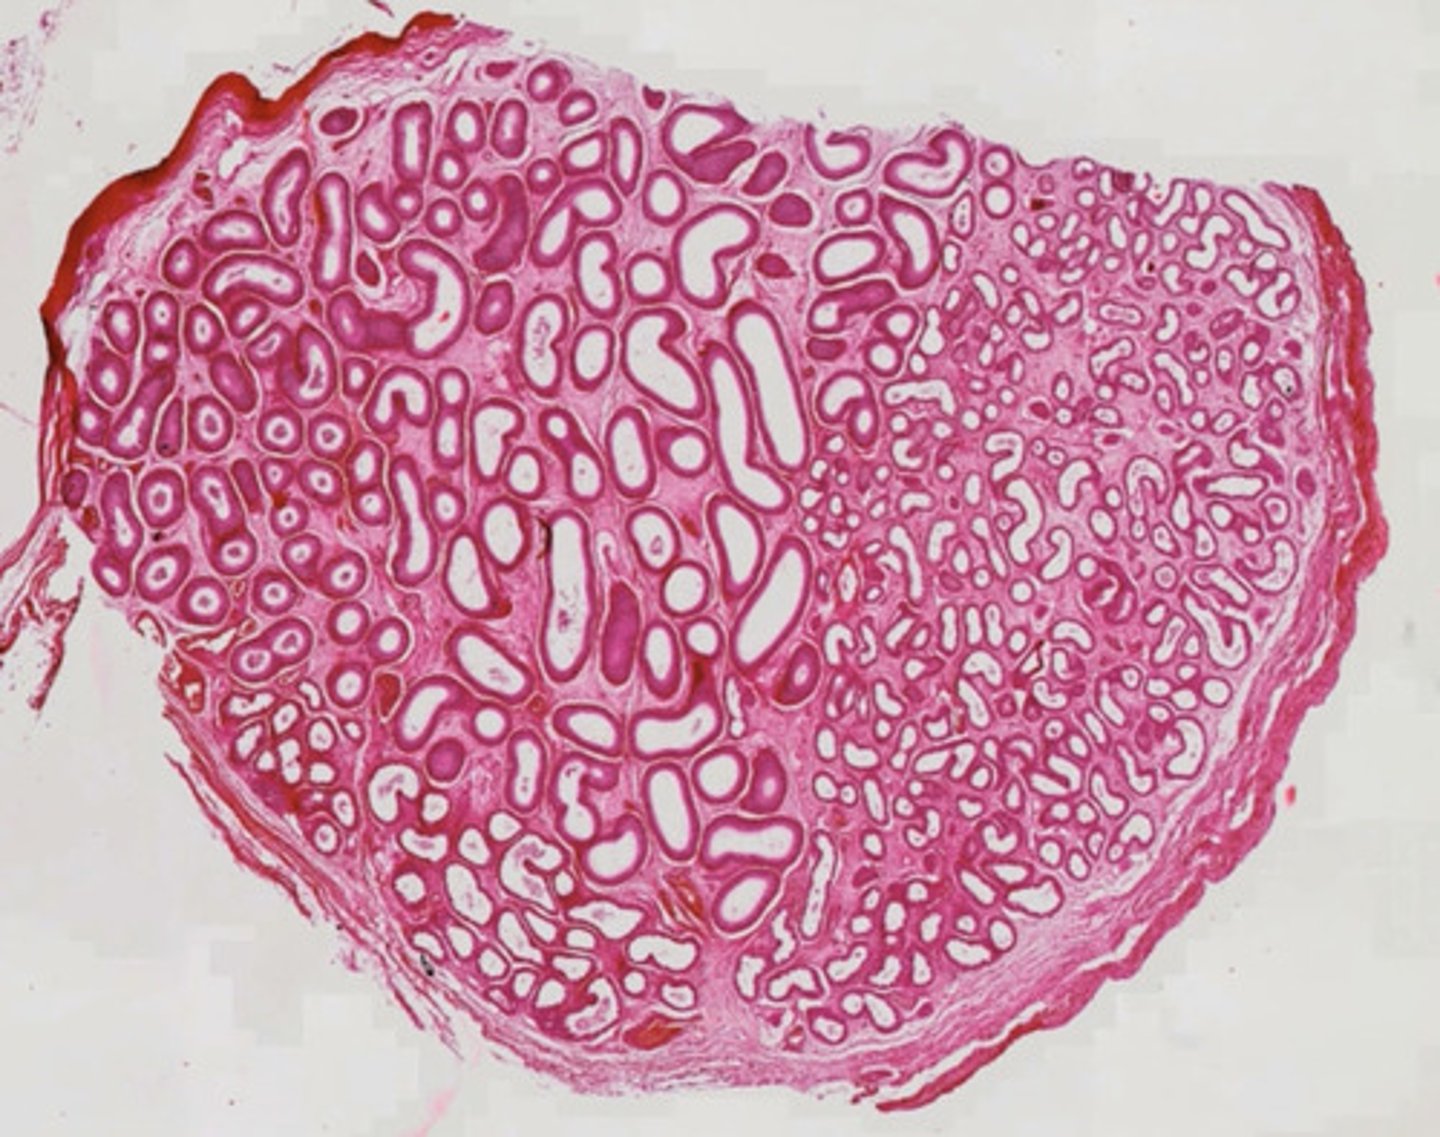

Skóra owłosiona - przekrój poprzeczny (H+E)